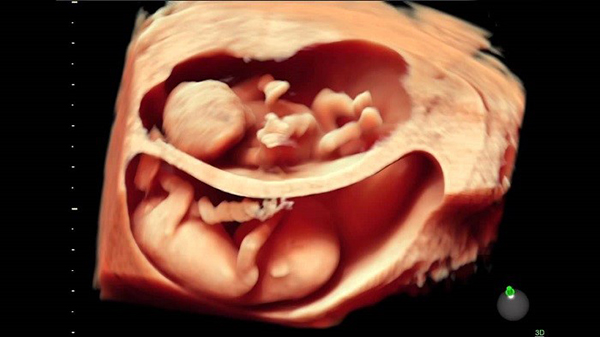

Từ tuần 7 thì con đã chớm hình thành các đầu ngón tay, ngón chân có màng, phần đuôi mở rộng của xương cụt cũng dần biến mất. Hệ thần kinh đã bắt đầu phân nhánh, tạo thành hệ sơ khai. Con đã dần xuất hiện mí mắt và cả ống thở kéo dài từ cổ họng đến nội tạng phổi.

Thai nhi 7 tuần phát triển bình thường có các đặc điểm như sau:

– Bàn tay, bàn chân dần dần xuất hiện các ngón kèm màng bảo vệ

– Phần xương đuôi bắt đầu co lại, và có thể đã biến mất.

– Các cơ quan nội tạng bé đang phát triển vượt trội, ống thở đã dần xuất hiện và vận chuyển oxy từ cổ họng đến các nhánh phổi

– Bé đã có mí mắt, và nhiều bé màu mắt cũng dần được lộ ra ngoài.

– Tai đã dần hình thành, lưỡi và các chân răng cũng đã có.

– Bộ phận sinh dục chưa phát triển toàn diện, khó có thể biết được là trai hay gái.